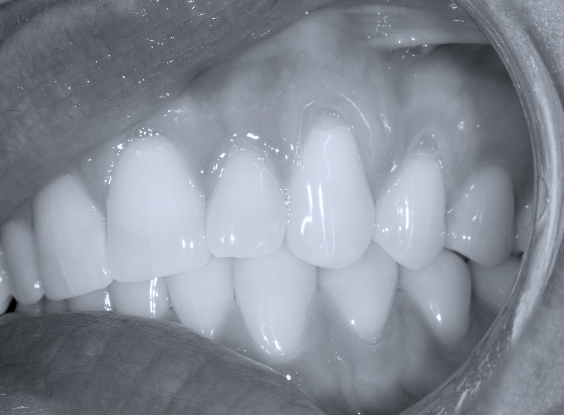

O principal tratamento é realizado através de procedimentos cirúrgicos para obter o recobrimento radicular, tal tratamento visa o recobrimento da(s) superfície(s) de raiz(es) exposta(s) por tecido gengival. O tecido é coletado e manipulado de forma cuidadosa, para que seja posicionado no lugar proposto.

Existem diversas técnicas de cirurgia desenvolvidas para solucionar problemas específicos. A técnica escolhida depende de diversos fatores.